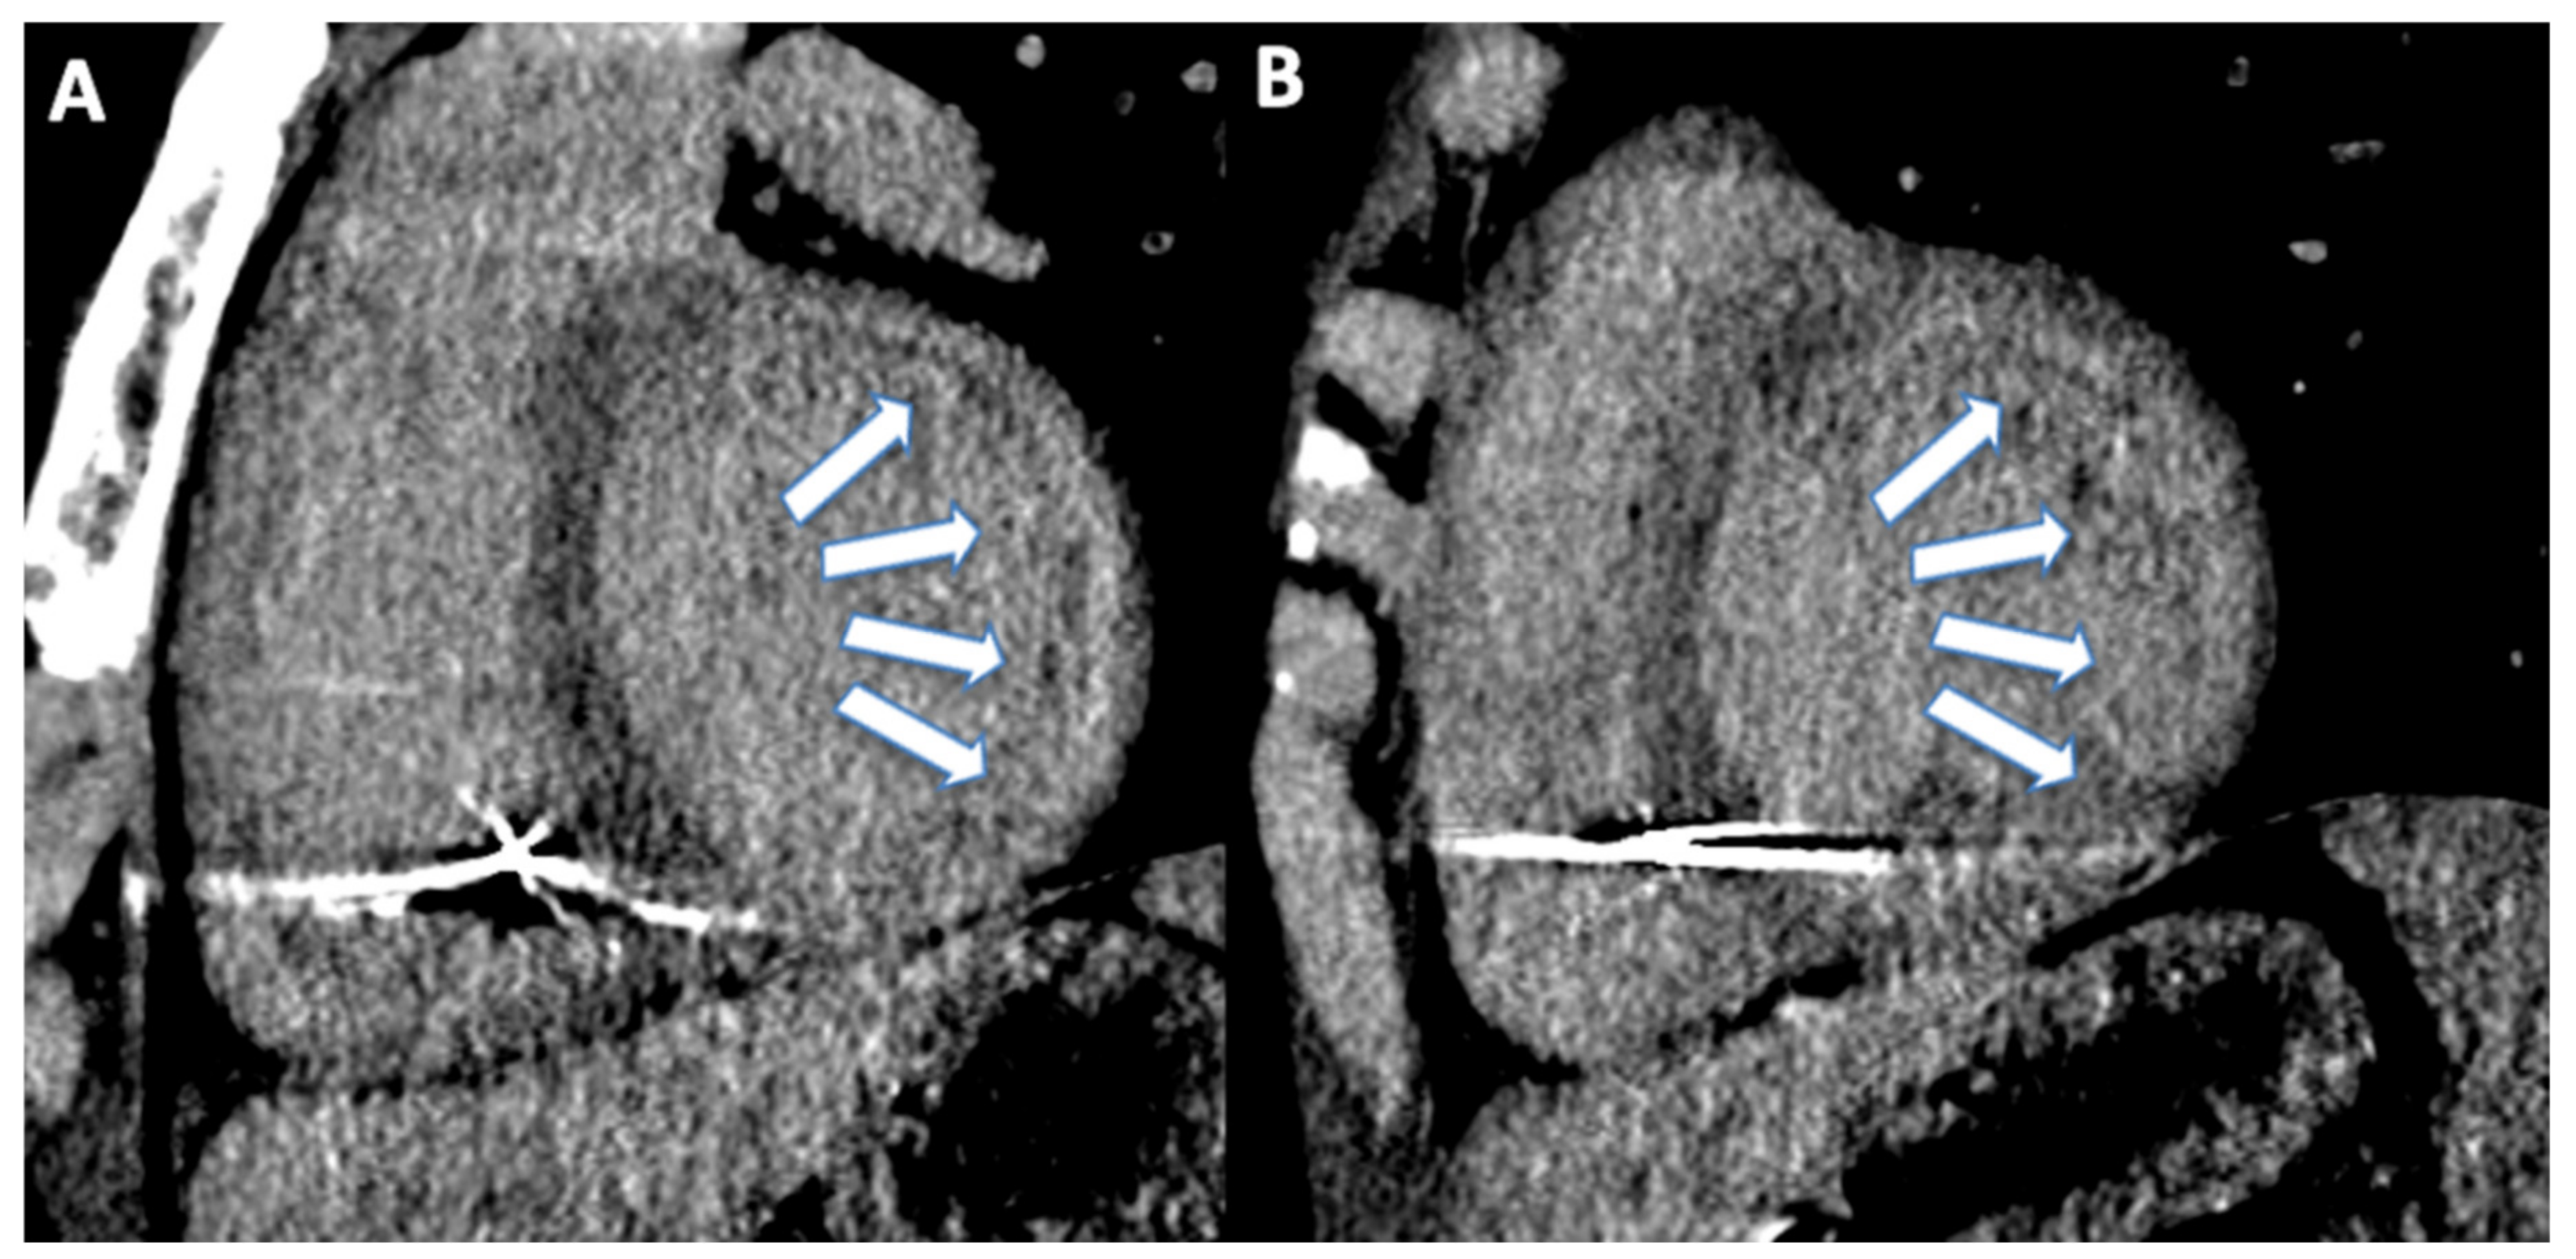

- Esposito, A.; Palmisano, A.; Barbera, M. Cardiac Computed Tomography in Troponin-Positive Chest Pain: Sometimes the Answer Lies in the Late Iodine Enhancement or Extracellular Volume Fraction Map. JACC Cardiovasc. Imaging 2019, 12, 745–748. [Google Scholar] [CrossRef] [PubMed]

- Van den Hoogen, I.J.; Gianni, U.; Al Hussein Alawamlh, O. What atherosclerosis findings can CT see in sudden coronary death: Plaque rupture versus plaque erosion. J. Cardiovasc Comput. Tomogr. 2020, 14, 214–218. [Google Scholar] [CrossRef]

- Motoyama, S.; Ito, H.; Sarai, M.; Kondo, T.; Kawai, H.; Nagahara, Y.; Harigaya, H.; Kan, S.; Anno, H.; Takahashi, H.; et al. Plaque Characterization by Coronary Computed Tomography Angiography and the Likelihood of Acute Coronary Events in Mid-Term Follow-Up. J. Am. Coll. Cardiol. 2015, 66, 337–346. [Google Scholar] [CrossRef]

- Chang, H.-J.; Lin, F.Y.; Lee, S.-E.; Andreini, D.; Bax, J.; Cademartiri, F.; Chinnaiyan, K.; Chow, B.J.; Conte, E.; Cury, R.C.; et al. Coronary Atherosclerotic Precursors of Acute Coronary Syndromes. J. Am. Coll. Cardiol. 2018, 71, 2511–2522. [Google Scholar] [CrossRef]